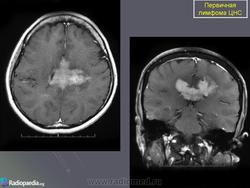

Первичные лимфомы ЦНС. Вс, 22/05/2011 - 21:45 #1 Катенёв Валенти... Не на сайте Был на сайте: 7 лет 5 месяцев назад Зарегистрирован: 22.03.2008 - 22:15 Публикации: 54876 Продолжение.Приложения:

Продолжение.